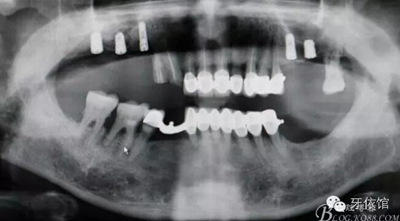

術(shù)后X光片

患者男,64歲,左上6,7、右上6,7缺失,6年前做上頜球帽附著體,前幾日右上3,4,5烤瓷牙脫落,右上3,4冠折,右上5三度松動(dòng)。x光示根尖周大面積陰影。

(2)右上5拔除,右上5,6,7植入三顆植體且右上5為即可,右上6,7外提(改良)同期植入。